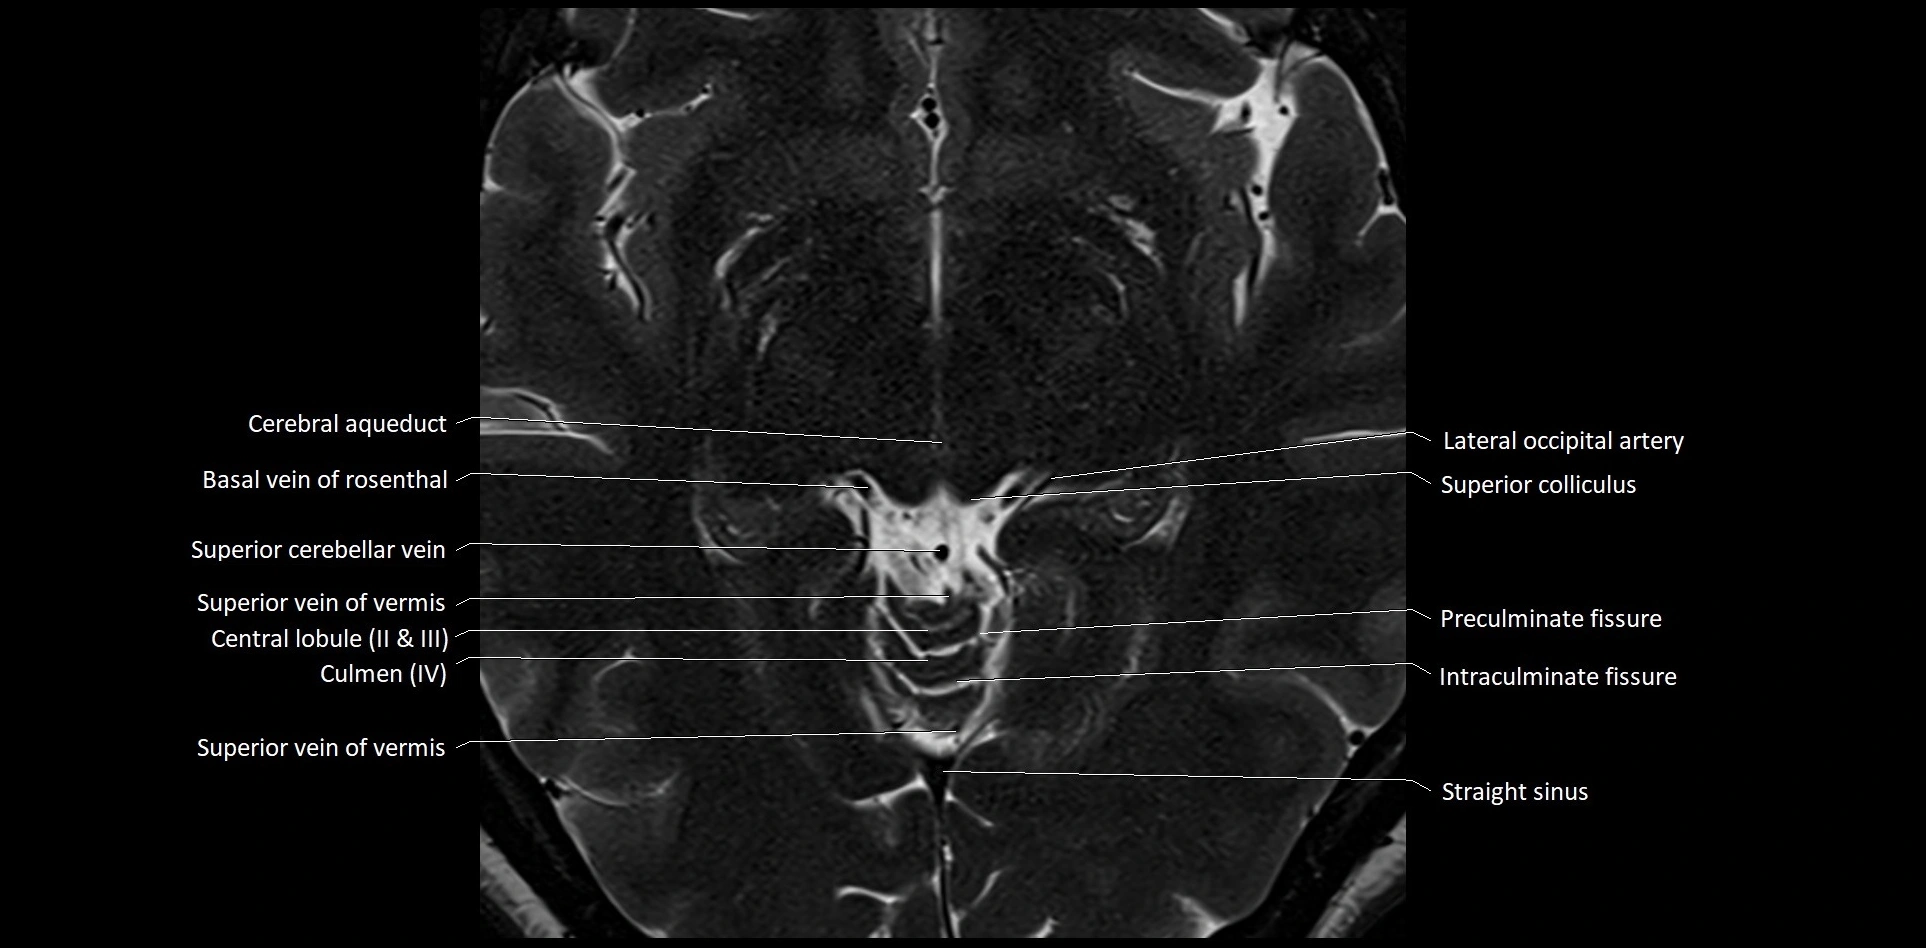

MRI images